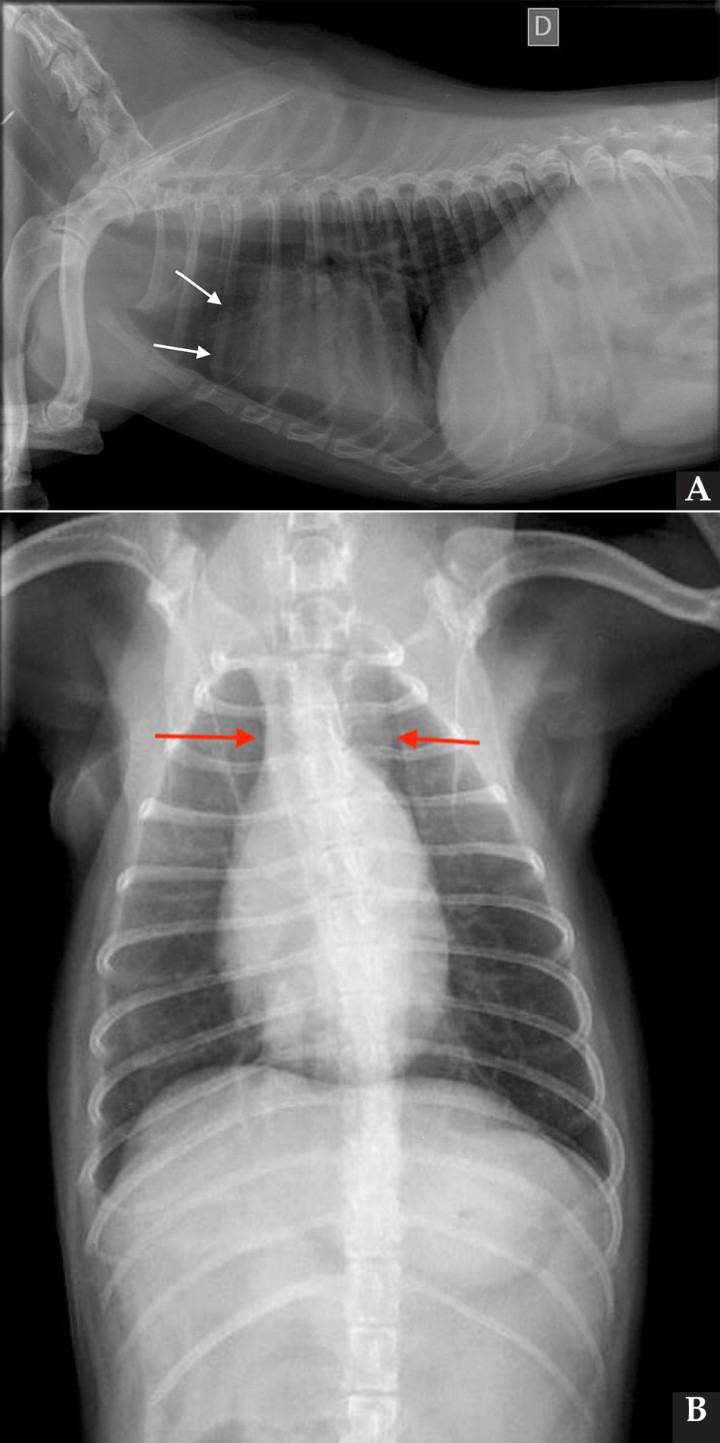

Se realizaron radiografías torácicas y en la proyección lateral derecha se observó, craneal a la silueta cardiaca, una opacidad tejido blando mal definida que producía efecto silueta positivo con esta. La tráquea se visualizó desplazada dorsalmente y el atrio izquierdo aumentado de tamaño. El parénquima pulmonar mostraba un aumento de opacidad en su área caudodorsal, compatible con un patrón pulmonar intersticial no estructurado difuso, el cual se consideró normal debido a que la radiografía fue tomada en fase espiratoria inicial y a la condición corporal del paciente. En la proyección ventrodorsal, el mediastino craneal se observó en el límite superior de tamaño, presentándose un tamaño dos veces superior a la anchura de la vértebra torácica (Fig. 1). Este cambio es compatible con una imagen artefactual secundaria a la leve rotación que presenta la radiografía y a la condición corporal del paciente. El diagnóstico radiológico más probable fue una masa mediastínica craneoventral y cardiomegalia izquierda. En la ecocardiografía transtorácica se confirmó el diagnóstico de enfermedad degenerativa de la válvula mitral (EDVM), presentando engrosamiento, prolapso e insuficiencia valvular, dilatación del atrio izquierdo (AI/AO=1,9) y leve aumento de las dimensiones diastólicas del ventrículo izquierdo normalizado al peso del paciente (NLVDD=1,7). Las presiones de llenado intracardiacas se estimaron como normales, ya que el flujo transmitral presentó un patrón de relajación anómala y la velocidad pico de E fue de 0,8 m/s. En función de estos hallazgos se confirmó el diagnóstico de enfermedad degenerativa valvular mitral con cardiomegalia izquierda y sin hallazgos compatibles con insuficiencia cardiaca congestiva, por lo tanto en estadio ACVIM B2. En las vistas ecocardiográficas paraesternal derecha de 4 cámaras y apical izquierda de 4 cámaras se visualizó una estructura redondeada y anecógena de 15 mm, con flujo sanguíneo en Doppler color, adyacente al corazón (Fig. 2). Este hallazgo es compatible con dilatación aneurismática de las estructuras vasculares o las cavidades cardiacas, si bien no se pudo establecer continuidad con ninguna de ellas en la ecografía. La valoración con Doppler pulsado de los tractos de salida del ventrículo izquierdo y derecho mostró la repetición de un perfil de flujo con disminución del área bajo la curva en el segundo latido con respecto al precedente.

<p>Ecocardiografía. (<strong>A</strong>) Vista apical izquierda de 4 cámaras optimizada para ADD. Engrosamiento de la válvula mitral (VM), dilatación moderada de atrio izquierdo (AI) y ventrículo izquierdo (VI). Estructura redondeada y anecógena de 15 mm con flujo sanguíneo (AAD), adyacente al corazón. AD: atrio derecho. (<strong>B</strong>) Vista paraesternal derecha de 4 cámaras optimizada para el atrio izquierdo. Estructura redondeada y anecógena (AAD) asociada al corazón. AD: atrio derecho.</p>

Figura 2

Ecocardiografía. (A) Vista apical izquierda de 4 cámaras optimizada para ADD. Engrosamiento de la válvula mitral (VM), dilatación moderada de atrio izquierdo (AI) y ventrículo izquierdo (VI). Estructura redondeada y anecógena de 15 mm con flujo sanguíneo (AAD), adyacente al corazón. AD: atrio derecho. (B) Vista paraesternal derecha de 4 cámaras optimizada para el atrio izquierdo. Estructura redondeada y anecógena (AAD) asociada al corazón. AD: atrio derecho.